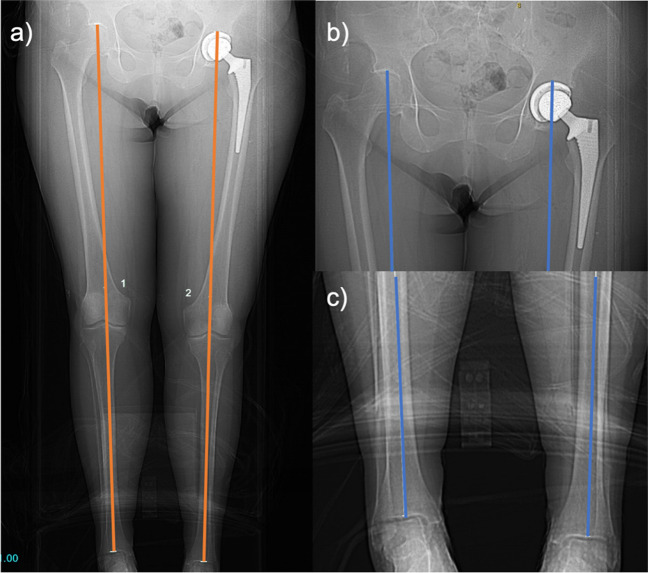

Objective: To compare the magnitude of post-arthroplasty leg length discrepancy (LLD) and incidence of clinically significant LLD measured on CT scanogram using a commonly used measurement method (from the acetabular apex to tibial plafond) to an alternative technique avoiding the use of the acetabular prosthesis as a landmark and to assess inter-observer and intra-rater reliability of the new technique.

Materials and methods: In this retrospective study, post-arthroplasty LLD measurements were conducted in 100 hips by two interpreters on CT scanogram scout views from the acetabular apex to the tibial plafond (AA-TP) and the inter-teardrop line to the tibial plafond (IT-TP). Aggregate means and proportions of clinically relevant LLD (≥ 10 mm) were compared between methods. Inter-rater reliability was calculated, and both interpreters repeated measurements on ten randomly selected patients to calculate intra-rater reliability.

Results: The commonly used AA-TP technique overestimated LLD by 3.7 mm compared to the IT-TP technique. The odds of LLD measurement exceeding the clinically significant threshold of 10 mm were 3.8 times higher when using the AA-TP technique. Excellent inter-rater (ICC 0.984, 0.958) and intra-rater reliability (ICC > 0.9) were found for both techniques.

Conclusion: CT scanogram measurements from the acetabular apex to the tibial plafond often overestimate operative limb length due to reference landmarks in different axial planes. Measurements from the inter-teardrop line to the tibial plafond yield significantly lower LLD values, possibly reflecting actual limb length better. The authors recommend using the inter-teardrop line and tibial plafond as reference landmarks to improve LLD assessment accuracy post-arthroplasty.